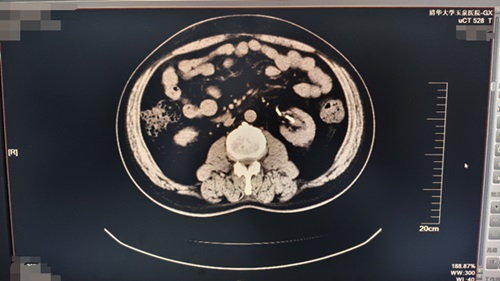

患者,男,46歲,主因左側(cè)腰腹部間斷性疼痛10天。于我院查泌尿系CT示左腎鹿角狀結(jié)石、右腎結(jié)石收入院。后在可控負(fù)壓吸引下行輸尿管軟鏡鈥激光碎石術(shù)治療腎結(jié)石。

術(shù)前視圖如下:

由CT可見(jiàn):患者左側(cè)腎盂輸尿管支架術(shù)后改變,較術(shù)前左腎結(jié)石體積基本消失,原左側(cè)輸尿管上段結(jié)石、左腎盂-輸尿管結(jié)合部擴(kuò)張較前未見(jiàn)。